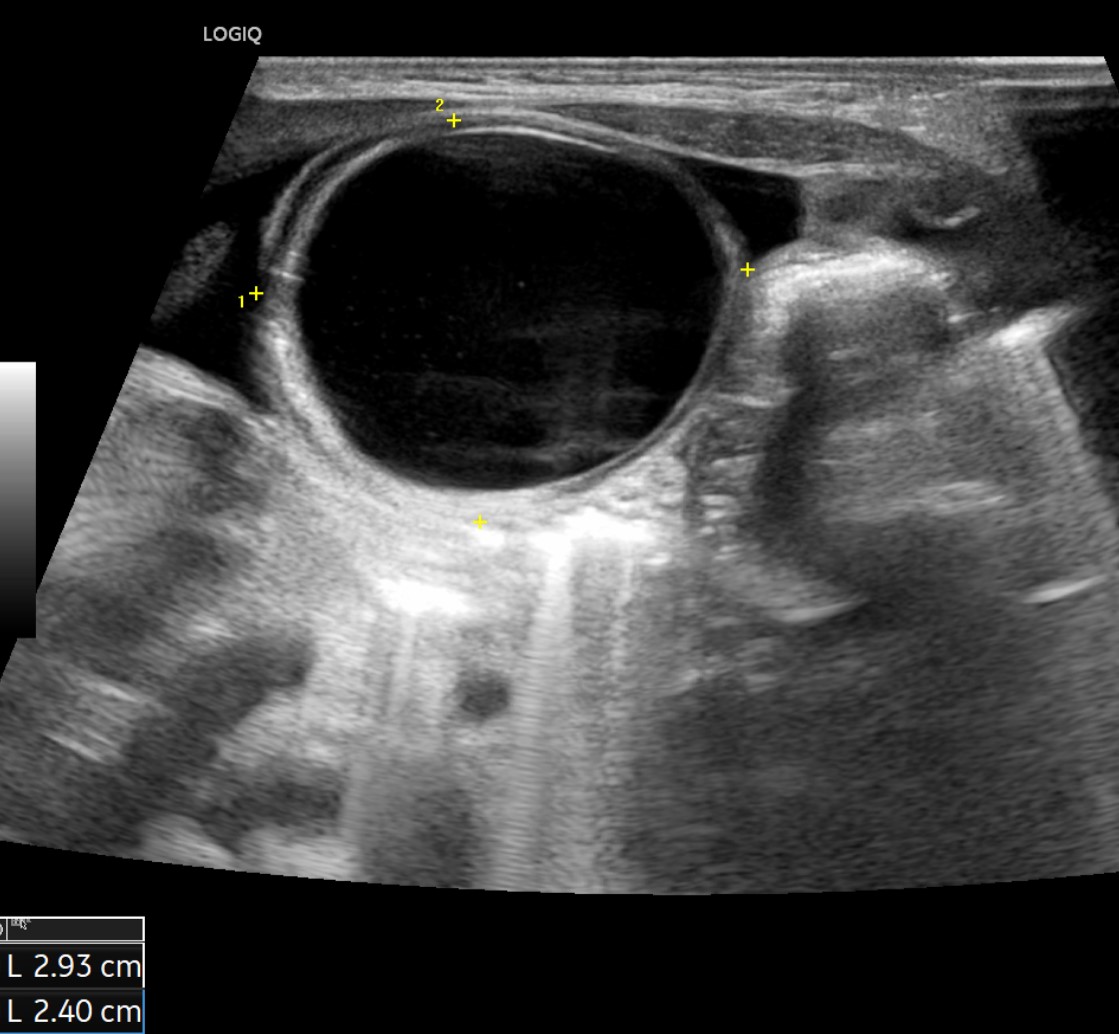

[359,Pediatric [Ped]] 1/F,Abdominal cyst was detected on prenatal ultrasound.

Modality US,

실제 이미지 실제 이미지